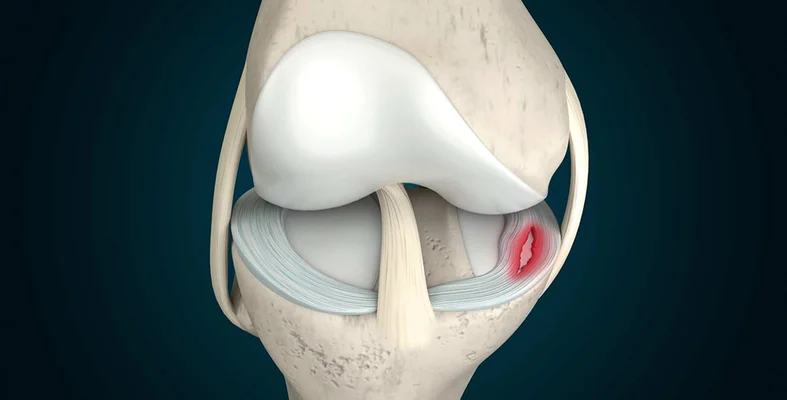

يعتبر الغضروف الهلالي هو عنصرًا أساسيًا في مفصل الركبة، حيث يتكون من قطعتين من النسيج الغضروفي؛ كما يقع هذا الغضروف بين عظم الفخذ وعظم الساق، ويتميز بشكله الذي سشبه الهلال؛ كما تعمل هذه الأنسجة على حماية المفصل وتسهيل الحركة من خلال تقليل الاحتكاك بين عظمي الفخذ والساق كما تلعب دورًا مهمًا في توزيع الوزن على مفصل الركبة، وهذا يعزز من قدرته على مقاومة الصدمات والتأثيرات الخارجية التي تنتج عن أنشطة الحركة مثل المشي والجري؛ كما يعرف الهيكل الغضروفي الذي يتخذ شكل حرف C في مفصل الركبة (بين عظام الفخذ والساق) باسم الغضروف الهلالي ويوجد غضروفان هلاليان في كل ركبة، أحدهما داخلي والآخر خارجي يعمل الغضروف الهلالي كوسادة لضمان توافق أسطح الغضاريف مع بعضها البعض.

الغضروف الهلالي هو مصطلح يشير إلى الحالة المرضية التي تتعلق بالغضروف الموجود بين مفاصل الركبة، وهو مرض يعيق الحركة يظهر الغضروف الهلالي غالبًا عند الرياضيين، ويمكن أن يحدث لدى الشباب والراشدين وكبار السن في الغالب يكون السبب في ظهور هذه الحالة لدى الشباب هو الإصابات الرياضية، بينما تتسبب الشيخوخة وتراجع مستوى السوائل في المفاصل في حدوثها لدى كبار السن.